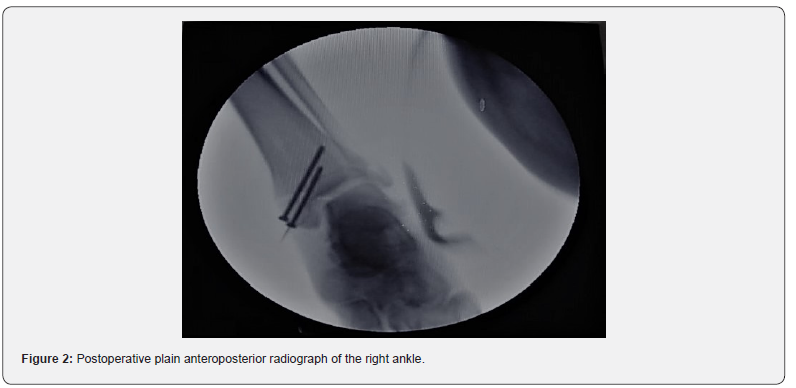

Surgery was performed under spinal anesthesia using a C-arm image intensifier. The medial malleolar fracture was fixed using two screws and the hemi-Castaing technique was done to repair the complex lateral ligament of the ankle [6] (Figure 2). Only the technique of lateral ankle ligament plasty is described below.

The tendon is hemi-sected proximally for half of its diameter and then split over the length of the tendon to the level of the most distal point of the fibula, releasing an 8-cm cord of tendon, free proximally, but remaining firmly anchored at its point of insertion at the base of the fifth metatarsal, the so-called hemi-tendon (Figure 3b). A hole is then drilled through the distal part of the lateral malleolus, forming a tunnel running between the directions of the ATFL and CFL (Figure 3c). The hemi tendon is passed through the tunnel from back to front and sutured to itself distally. The foot is maintained in a neutral anatomical position while the sutures are progressively tightened until optimal tensioning is reached (Figures 2 & 3d) [9]. Postoperatively patients are kept in non-weightbearing plaster for two weeks and weight-bearing plaster for six weeks.